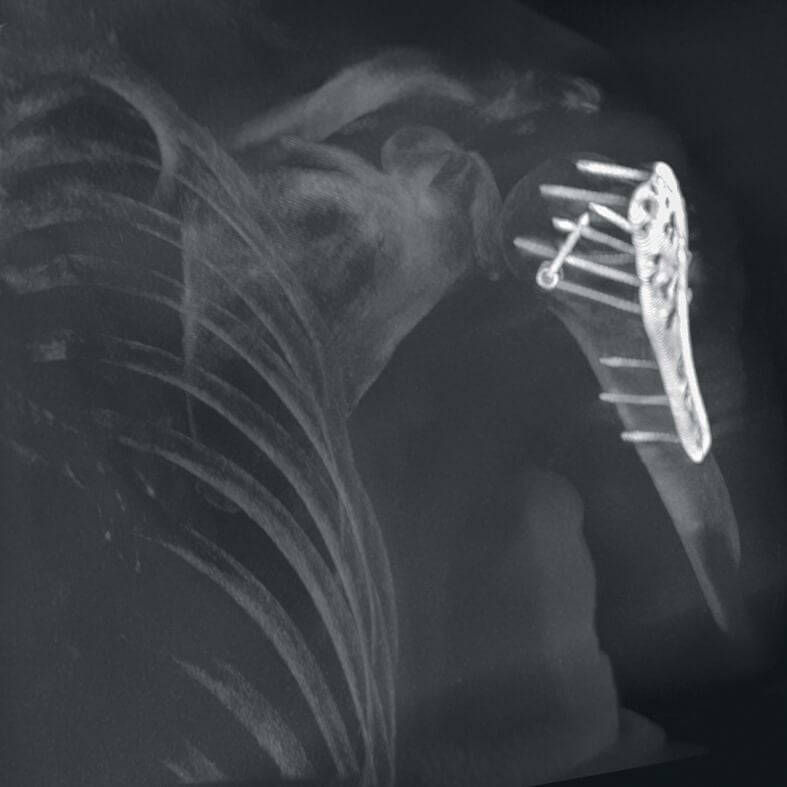

Полное отсутствие искажений снимков в сочетании с высоким динамическим диапазоном широко востребованы как при сложных операциях в нейрохирургии, сосудистой хирургии, инвазивной радиологии, так и в гибридных областях применения, а также в ортопедии, травматологии. В сосудистой хирургии особенно важны высокий динамический диапазон и пространственное разрешение, обеспечивающие детальную визуализацию даже мельчайших сосудов. Специализированное программное обеспечение SmartVascular позволяет проводить настройку системы для васкулярных операций и сосудистой хирургии.

Точная визуализация анатомических деталей, мягких тканей и костных структур обеспечивается за счет светочувствительной матрицы 3kх3k пикселей с высоким динамическим диапазоном.

Автораспознавание металла

Винты, пластины, импланты и хирургические инструменты автоматически распознаются при попадании в видимое поле аппарата. В этом случае происходит корректировка мощности дозы облучения для улучшения качества снимка.